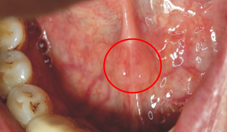

福台斯氏顆粒(Fordyce granules)為口腔內出現的皮脂腺增生,臨床特徵為多個黃色或黃白色的顆粒狀突起,常出現於兩側頰黏膜或嘴唇,有時也會出現在臼齒後區域,通常沒什麼症狀,偶爾會讓人有粗糙的「顆粒」感。許多成年人的口腔內都可以發現這樣的現象。因為這些皮脂腺本來就是人體的正常構造,出現於口腔內,並不會對口腔健康造成妨礙,所以也不需要任何治療。

福台斯氏顆粒(Fordyce granules)的特徵為多個黃色或黃白色的顆粒狀突起,常出現於兩側頰黏膜或嘴唇(左圖)。